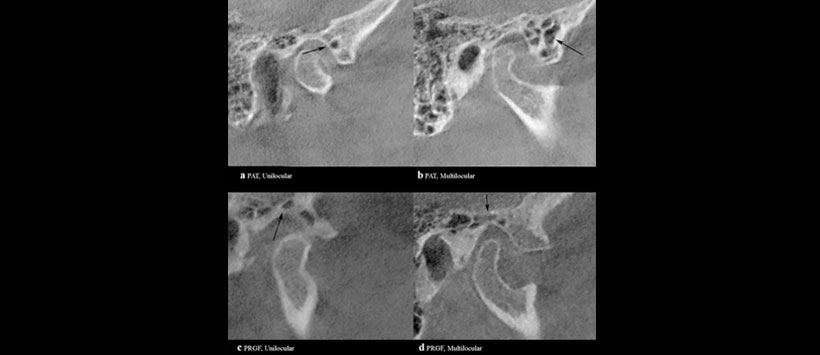

Obteniendo como resultado que la PAT está presente en un el 28,4% de los lados del hueso cigomático y PRGF en el 29,6%. También se detectó PAT bilateral en 176 (17.6%) pacientes y PRGF bilateral en 195 (19.5%). La edad media de los pacientes con PAT fue de 47,33 años y la de los pacientes. Con PRGF fue de 45.62 años. La apariencia multilocular se observó significativamente más a menudo que el tipo unilocular para ambos neumatizaciones. Los casos de PAT unilateral fueron leves, pero significativamente más altos que los casos de PAT bilateral. Mientras que no se observaron diferencias significativas entre los casos de PRGF unilaterales y bilaterales. (Figura 1)

En conclusión, PAT y PRGF se pueden evaluar más con precisión en imágenes CBCT que en radiografías simples. La presencia de PAT y PRGF son importante en términos de volumen óseo y resistencia, propagación de tumores, inflamación, y complicaciones de la cirugía de la ATM